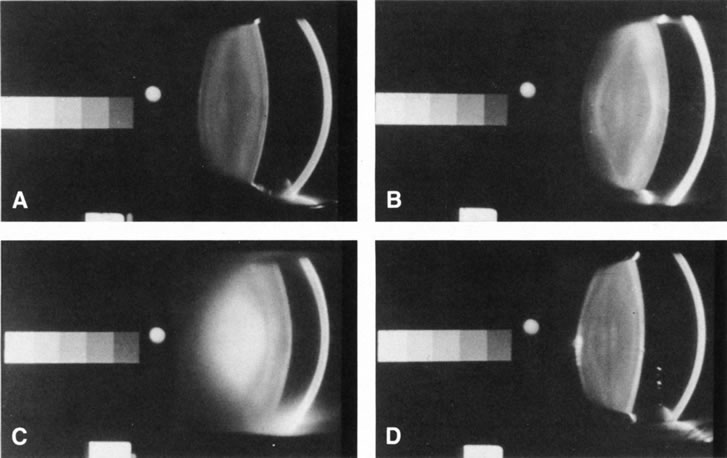

Fig. 5. Scheimpflug slit-lamp photographic images of: (A) normal; (B) cortical; (C) nuclear; and (D). Posterior subcapsular cataracts. The Scheimpflug method allows

for slit-lamp imaging wherein the entire lens is in focus. The

gray scale on the left of each image was built-in to aid standardization

of the image during densitometry (for objective quantification

of the opacities). Fig. 5. Scheimpflug slit-lamp photographic images of: (A) normal; (B) cortical; (C) nuclear; and (D). Posterior subcapsular cataracts. The Scheimpflug method allows

for slit-lamp imaging wherein the entire lens is in focus. The

gray scale on the left of each image was built-in to aid standardization

of the image during densitometry (for objective quantification

of the opacities).

comfort. The Scheimpflug camera (see below) was developed to

increase the depth of focus of images obtained with the slit lamp (Figs. 5 and 6) and is ideal for documenting slit images of the lens, and especially

nuclear cataracts.47–48 It uses a fixed narrow beam and obtains reproducible images in which the

whole-lens thickness is in focus. These images can be examined

by densitometry for statistical comparison with other images of the

same patient taken over time to document and track changes. The broad beam is useful for examining cortical cataracts especially spokes

the Oxford Scheimpflug camera (Marcher Enterprises, Hereford, U.K.). Figures 5 and 6 show Scheimpflug images of a normal lens and various types of cataracts

obtained using a Scheimpflug camera, and two ways to analyze these images

to obtain the mean density of various areas within the lens.48,50 Longitudinal studies, such as for following the progression of nuclear